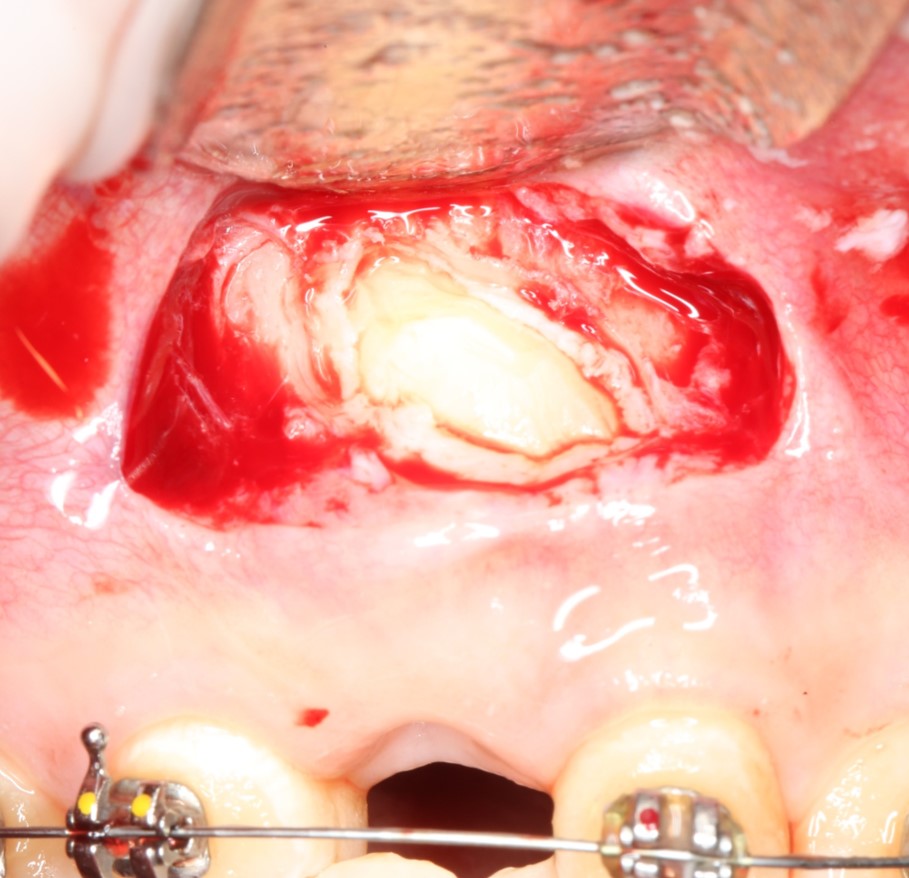

Как-то так:

когда мы понимаем этот принцип, то удаление даже самых сложных зубов становится очень простым и безопасным занятием и занимает не более 15-20 минут. Как, например, в этом случае, мы удалили ретинированный клык минут за десять. Хотя, в другой клинике обещали операцию в несколько часов.

Другими словами, «страшная» форма зуба, кривой корень или «ненормальное» положение зуба не являются чем-то осложняющим процесс удаления. Любую «страшную форму» можно представить как совокупность нескольких «нестрашных» — и спокойно приступать к операции.